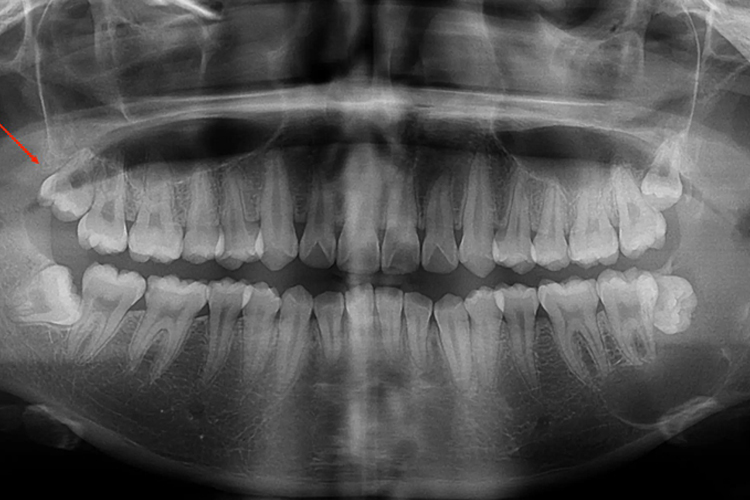

颊向阻生是阻生牙的一种,常见于下颌第三磨牙、上颌第三磨牙、上颌尖牙以及某些多生牙。颊向阻生一般属于水平阻生,观察患者口腔时可见牙齿排列拥挤,影像学检查可见朝向为颊向的阻生牙。